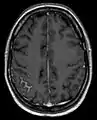

Screening involves an MRI scan to identify and diagnose tumors in the subarachnoid region of the brain. MRI can make a diagnosis even without an analysis of the cerebrospinal fluid but it can sometimes be difficult to detect because MRI scans cannot always pick up the problem.[18]

Meningeal carcinomatosis in a patient with breast cancer (contrast-enhanced axial T1-weighted MRI)